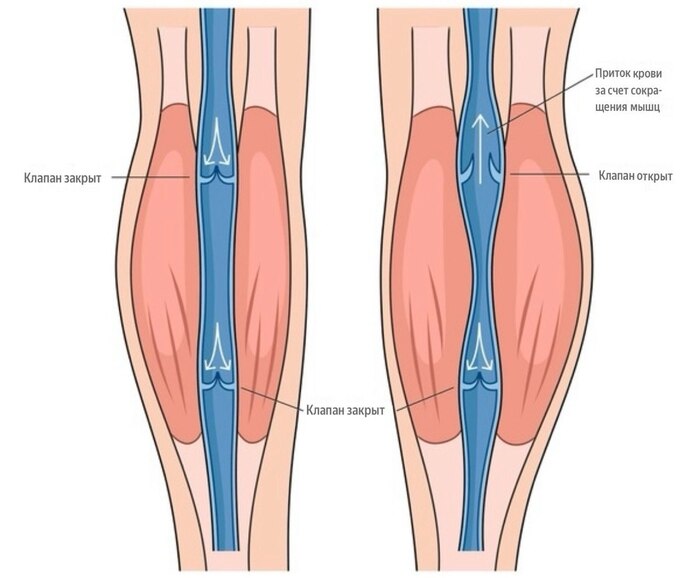

Вы когда-нибудь задумывались, почему кровь из ног и рук возвращается к сердцу, по сути течет вверх, а не течёт обратно вниз, несмотря на гравитацию? Давайте разберёмся!

Клапаны — маленькие «дверцы» внутри вен.

Внутри большинства вен есть клапаны, которые пропускают кровь только в одном направлении — к сердцу. Они мешают крови течь обратно вниз, особенно когда мы стоим или сидим.

Помощь мышц

Мышцы ног и рук работают как «помпы»: при сокращении они сжимают вены и помогают крови подниматься вверх. Самая большая нагрузка ложится на мышечно-венозную помпу голени, которая может выталкивать до 60% крови.

Движение — лучший помощник вен.

Когда мы долго сидим или стоим без движения, мышцы не сокращаются → венозная помпа «засыпает» → кровь застаивается → вены переполняются и клапанам становится сложнее справляться со своей задачей.